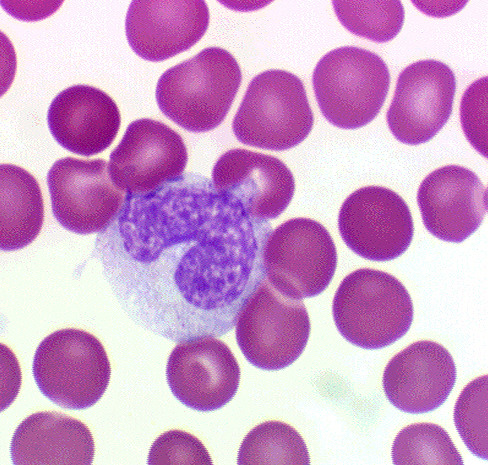

macrophage

White blood cell specializing in phagocytes

blood

Only fluid tissue of the body; transport